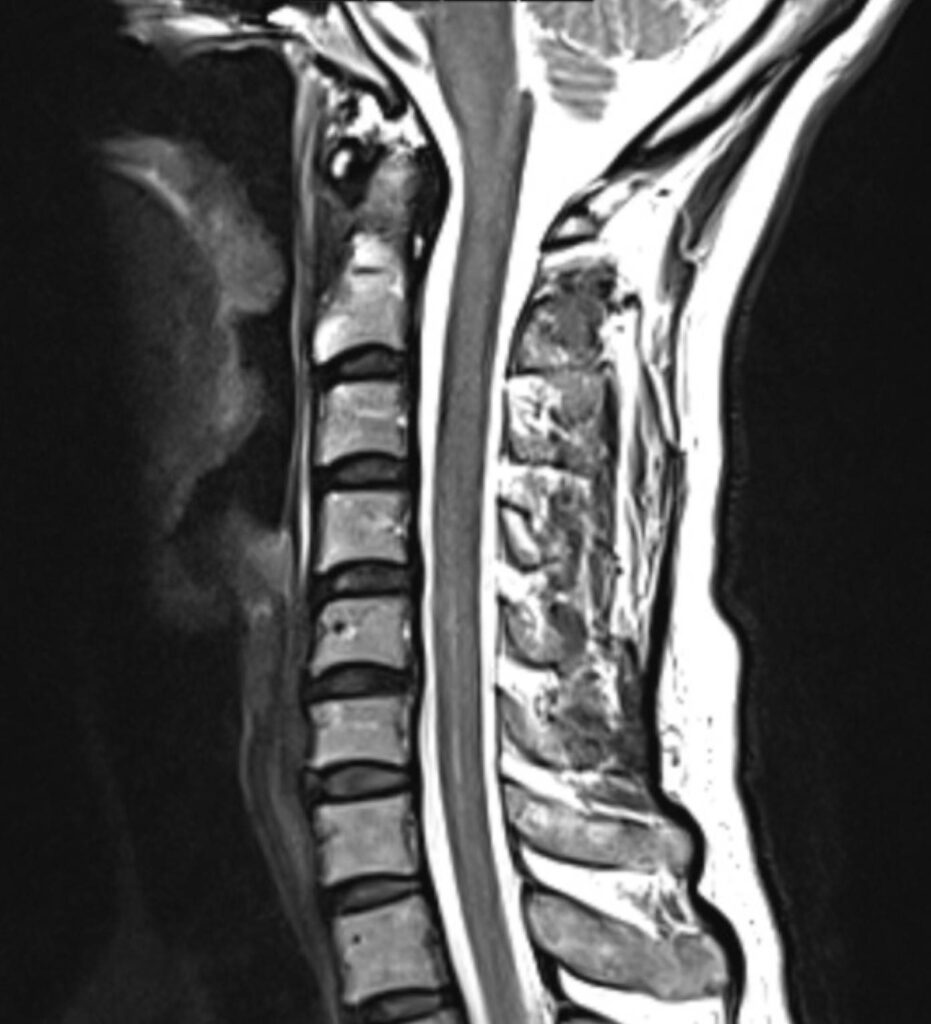

Die MRT Rücken Untersuchung gliedert sich in drei Hauptabschnitte und ermöglicht eine ganzheitliche Darstellung der Wirbelsäule. Die Wirbelsäule ist ein komplexes Konstrukt im Körperinneren und lässt sich durch eine Magnetresonanztomographie anhand MRT Bildern präzise darstellen.

Die MRT Wirbelsäule ermöglicht die Darstellung des Rückens mit Hilfe von einem starken Magnetfeld und Radiowellen. Die MRT des Rückens ist ungefährlich und schmerzfrei. Das bildgebende Verfahren verwendet bei einer Magnetresonanztomographie keine ionisierende Strahlung.

Bei einer Wirbelsäule MRT können sowohl knöcherne Strukturen als auch Weichteile erkannt und folglich untersucht werden. Dadurch eignet sich die MRT Wirbelsäule besonders gut, um Schmerzen mit unklarer Ursache im Rücken und der Wirbelsäule abzuklären. Denn auf den MRT-Bildern des Rückens können Schäden an der Wirbelsäule, den Bandscheiben und am Rückenmark erfasst werden.

Mögliche Erkrankungen an diesen Strukturen sind mit der nicht-invasiven bildgebenden Methode, wie es die Kernspintomographie bzw. Magnetresonanztomographie ist, bereits in frühen Stadien erkennbar, was für viele Patienten die Aussichten auf eine erfolgreiche Therapie erhöht bzw. die Prognose verbessert.